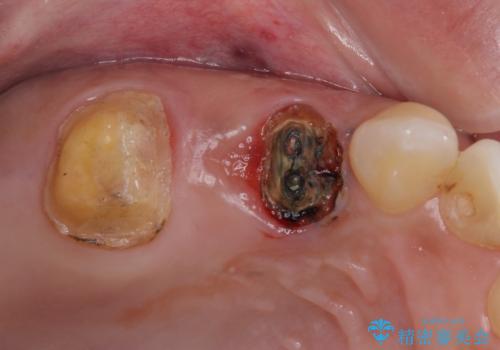

レントゲン写真などで診査した結果、奥歯の銀歯の下にはむし歯が多く存在し、右上の奥歯は歯根が破折していました。

破折した歯を抜去し、インプラントによる補綴を行うこととしました。